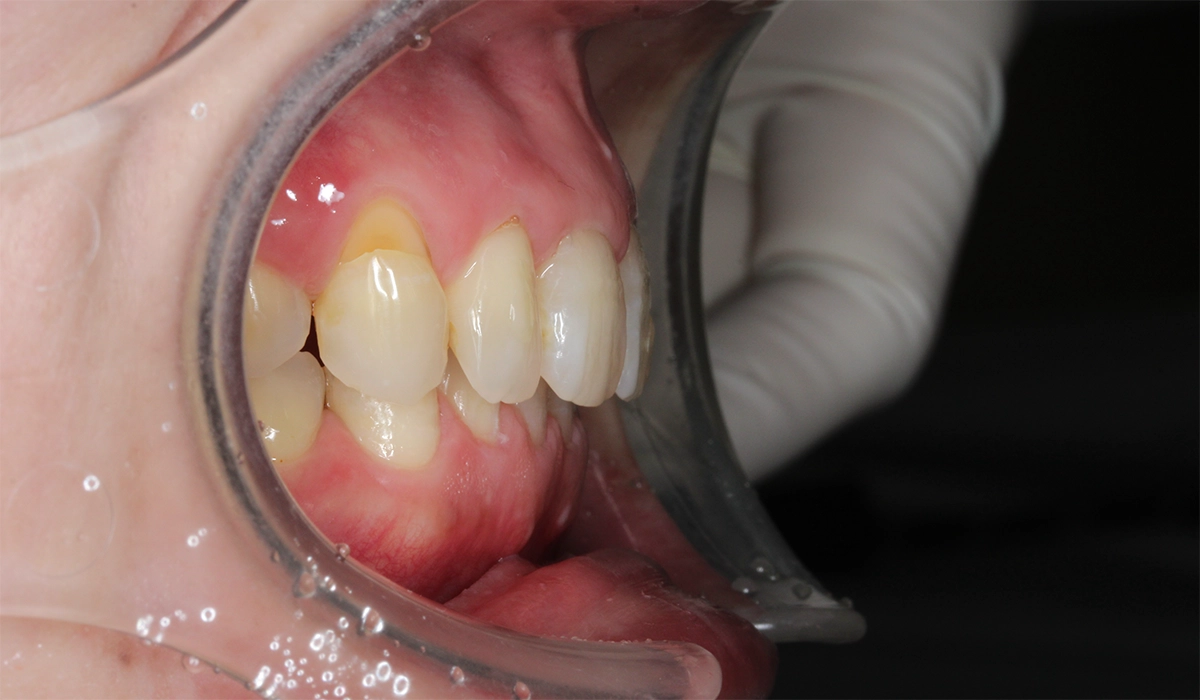

術前:右側